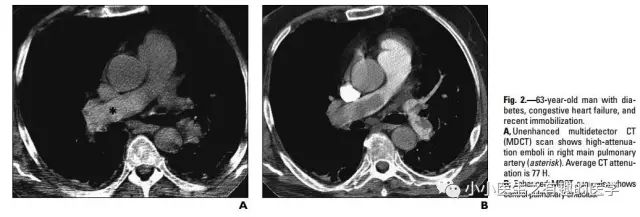

上面图片的英文原版

↓↓↓

星号的地方。